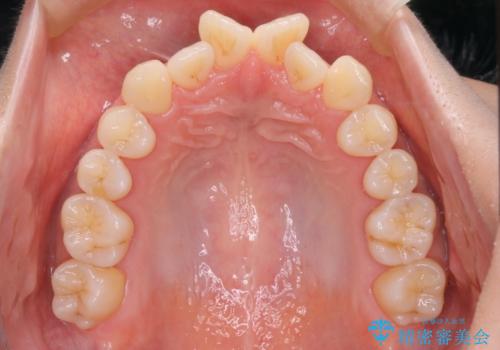

- 上の前歯のデコボコが気になるということで来院されました。

叢生量(デコボコ)が多いため、上下左右4番目の歯を抜歯してワイヤー矯正を行う治療計画を立てました。

主訴である前歯のデコボコが改善され、噛みあわせも綺麗になりました。

歯肉退縮もなく、予定通りに治療を終えることができ良かったです。